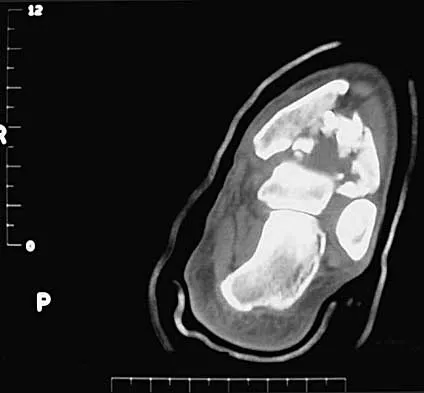

A 32-year-old man sustained a closed injury after falling 25 feet from a roof. His ankle and foot are severely swollen. Radiographs and CT scans are shown in Figures 29a through 29d. Initial management should consist of